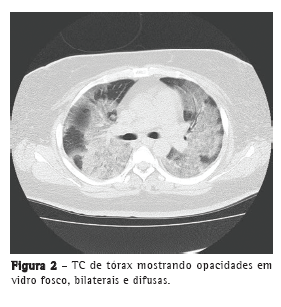

Relatamos um caso, tratado com sucesso, de pneumonia por VPI3 simulando pneumonia por influenza em uma paciente asmática de 31 anos de idade. A paciente apresentou febre alta (39.5°C), fadiga geral, dor articular sistêmica e anorexia durante dois dias antes de ser encaminhada a nosso centro médico. Era fumante e apresentava história de tabagismo (20 anos maço) e de asma brônquica (sem uso atual de medicação). A paciente também apresentava diabetes mellitus mal controlada e índice de massa corporal de 30 kg/m2. A radiografia de tórax revelou opacidades em vidro fosco difusas em ambos os pulmões (Figura 1). Exames laboratoriais revelaram reação inflamatória grave (proteína C reativa = 19,2 mg/dL e VHS = 83 mm/h). A paciente apresentou insuficiência respiratória grave e SpO2 de 80% em ar ambiente na primeira visita e passou a receber oxigenoterapia com ventilação não invasiva com pressão positiva. Devido à insuficiência respiratória grave, não foi realizada lavagem broncoalveolar. Embora o resultado de um teste rápido para detecção de antígeno de influenza tenha sido negativo, a paciente recebeu diagnóstico de pneumonia por influenza com base em sintomas semelhantes aos da gripe e em achados radiológicos, tais como opacidades difusas em vidro fosco (Figura 2).